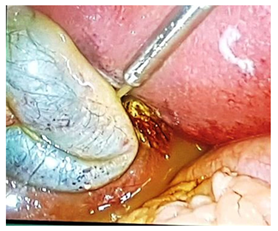

From the month of November 1, 2016 to January 5, 2016 laparoscopic surgery was performed over 26patients with symptomatic gall bladder diseases, thyroid tumor and appendicitis. These surgeries were performed in the Bahawal Victoria Hospital. We have used Olympus OTV-Si video processor, Dolphine Moercellator, endoscopic camera and other equipment of Dolphine Company. Before surgery consent was taken from all the patients. Illness which presented by most of the patients were pain in right hypochondria (RHC), vomiting, abdominal pain and nausea. Patients were sent for biopsy by various tests like x-ray, ultra sound, R/h blood tests and few others. The complete medical, surgical, physical and family history was considered to prevent the risk factors during surgery and post surgery infections. After pre-operational findings and diagnosing disease laparoscopic surgery was performed under general anesthesia. The patient’s consent was signed approved by Ethics Committee before surgery according to the standard laws of ethics of Bahawal Victoria Hospital. Among these 26 patients 18 were female and 8 were male and their average age was 36.7years ranged between ages 12 to 65years, belonged to middle and lower middle class. Their past history was nonalcoholic and nonsmoker. Surgery posture of patient and gall bladder position are described below (Figure 1).

Figure 1 Separation method of gall bladder full of stones from other organs.

Laparoscopic procedure was carried out under general anesthesia and a small incision is made around the belly button to insert camera. Two more incisions were made nearby to insert other instruments. To separate cavity carbon dioxide gas was used. Arties were clipped with titanium to block the arteries taking blood towards organ that we want to remove like gall bladder and it is taken out through umbilical port (Figure 2). This all procedure took 45minutes in average and patients were sent to recovery room for 15 minutes, later shifted to ward and discharged after one day.